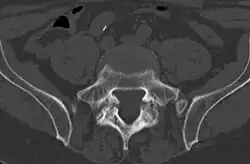

Bone scintigraphy showing black marks where pelvic bone damage has occurred.

Also known as a bone scan, bone scintigraphy involves the injection of a small amount of radioactive tracer into the bloodstream. This tracer decays and emits radioactive energy which can be detected by a special camera. The camera produces a black and white image where areas shown as dark black indicate bone damage of some kind. If there is a black spot in the lumbar vertebrae (e.g. L5) this indicates damage and potentially spondylolysis. If this test is positive, a CT scan is usually ordered to confirm spondylolysis.[16]